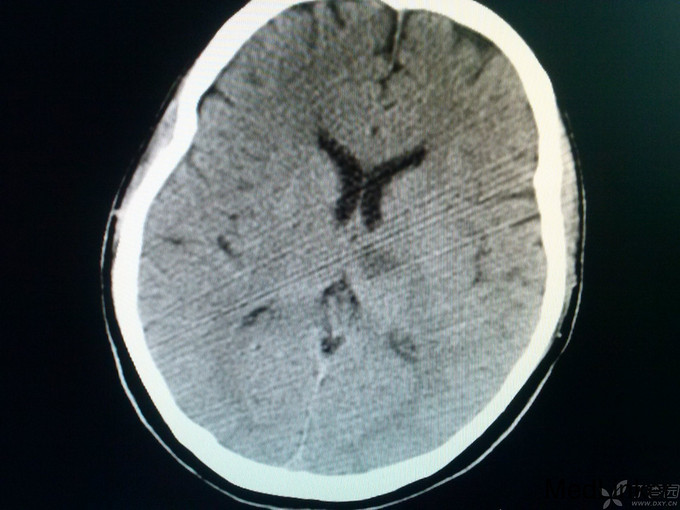

查体:体温36.0℃,脉搏60次/分,呼吸20次/分,血压120/80mmHg。平车推入病房,查体不合作。皮肤巩膜无黄染,胸前见手术瘢痕,双肺呼吸音粗,未闻及罗音,心室率72次/分,律绝对不齐,无病理性杂音,腹部膨隆,膀胱区叩诊为浊音,肝脾肋下未触及。神经系统专科查体:嗜睡,双瞳孔同大同圆,双眼直径3.0mm,对光反射灵敏,双侧鼻唇沟对称,咽反射(+),四肢对疼痛刺激有反应,肌张力正常,肱二头肌、肱三头肌肌腱及膝反射、跟腱反射均亢进,病理征:Babinski征L(+),R(+),颈无抵抗,Kernig征(-)。头CT:未见异常;入院后给予甘露醇125毫升间隔12小时静点一次,呋塞米20毫克间隔12小时静点一次。给予华法林2.5mg日一次口服、奥扎格雷80mg日一次静滴、活血化瘀、营养神经治疗。如是您是首诊患者,有何不同治疗方案?双抗+华法林、稳定斑块合适吗?理由呢? 4月27日: 患者嗜睡,叫醒后,问话能正确回答,患者不能识别物体的形状,左右肢体能识别,查体:嗜睡,双瞳孔同大同圆,双眼直径3.0m,对光反射灵敏,双侧鼻唇沟对称,咽反射(+),四肢活动可,肌张力正常,肱二头肌、肱三头肌肌腱及膝反射、跟腱反射均亢进,病理征:Babinski征L(+),R(+),颈无抵抗,Kernig征(-)。今日复查头CT:后续提供。同时华法林改为3.75mg日一次口服。病灶进展?还是? 4月28日 患者嗜睡,叫醒后,患者左右肢体失认,失算,尿量尚可,心电监护示:血压:96/70mmHg,心率140次/分,律不齐,血氧饱和度99%,现查体:嗜睡,呼吸平稳,肢体疼痛刺激可动,双瞳孔直径3.0mm,对光反射灵敏,双巴氏征(+)。双下肢无浮肿。给予低分子肝素4100单位间隔12小时皮下注射,患者心室率快,给予西地兰0.2mg静推。病灶进展?还是? 5月1日 患者处于嗜睡状态,但嗜睡时间较前明显缩短,问话可答,但答非所问,看似条理清晰,实则“子无须有”,呈现“虚构现象”,如问“几个孩子”,说“1个”,“男孩还是女孩”,答曰“男孩”,实则没有;问“什么水果”,有时能答对,绝大多数回答错误;但患者说话声调低、音量小,复述正常,心电监护示:血压107/77mmHg,心率89次/分,SPO2:98%,查体:嗜睡状态,丘脑性失语,无面瘫,双瞳孔直径3.0mm,对光反射灵敏,双眼上视、下视受限,以下视明显,四肢肌力5级,肌张力正常,双巴氏征(+)。 4月29日CT:

诊断: 1.BVTS 2.风心病,瓣膜置换术后 3.房颤